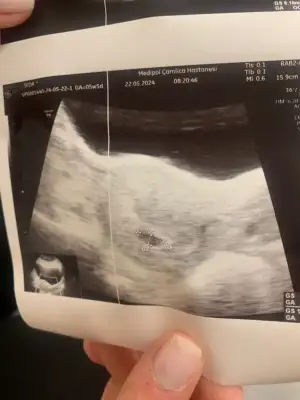

Çok şükür canımcinnabon kızlar selam çok şükür bugün keseyi gördüm ben de 5+5

her sey yolunda haftaya insallah kalp atışını duyarız dedi dr

Süper habercinnabon kızlar selam çok şükür bugün keseyi gördüm ben de 5+5

Valla bir sey demedi tam kuzum sadece her sey yolunda dedi dış gebelik vs değil emin olduk artık dedi :) size de fotosunu atayımSüper haberbebek , yolk sac da varmıydı kesenin içinde

Öyle dediyse oluşmuştur bebek deValla bir sey demedi tam kuzum sadece her sey yolunda dedi dış gebelik vs değil emin olduk artık dedi :) size de fotosunu atayım

Evet kzuum karından baktı valla ben de hic sormadım yolk sac vs ama sorun yok dediyse yoktur herhalde yaÖyle dediyse oluşmuştur bebek dehadi inşallah kalp atışını da duyarsınız. Senin karından baktı galiba değil mi ? Bana vajinal bakmıştı o yüzden resim daha net